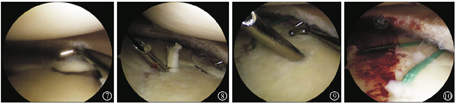

病例2 患者男,50岁,因"摔伤致右膝关节疼痛3 d"于2019年2月入院。入院查体:右膝关节肿胀压痛,活动受限,肢端血供感觉正常。入院查右膝CT(图5)及MRI(图6)提示右膝后交叉韧带止点无移位骨折,胫骨平台内后缘撕脱骨折累及内侧副韧带深层,诊断"反式Segond骨折"。完善术前准备后行右膝关节镜手术,麻醉下查体示右膝关节肿胀,前后抽屉及Lachman试验阴性,内外翻试验阴性。术中清理血肿后探查前后交叉韧带完整,后叉止点骨折无移位,发现内侧半月板后角撕裂行内侧半月板成形,内侧撕脱骨折块位于内侧半月板下方并翻转,细针定位骨折块位置后取膝关节内侧3 cm切口,分离至骨折部位,见骨折块菲薄约1 cm×0.5 cm×0.3 cm,连及内侧副韧带深层,考虑骨块太小空心钉固定困难改用缝线捆扎,复位后在关节镜监视下在骨折块前外及后外建立2 mm骨隧道,用硬膜外导针过线,将2号爱惜绑线捆扎复位骨折块,平台内侧放置小T型钢板作为阻挡支撑,将爱惜绑线打结在钢板上,术中关节镜探查骨折解剖复位(图7,图8,图9,图10)。术后复查CT进一步证实示骨折解剖复位(图11)。术后常规佩戴可调节膝关节支具伸直位固定并行直腿抬高锻炼股四头肌,术后2周开始膝关节0°~90°屈曲活动,术后6周膝关节0°~120°屈曲活动并拄双拐保护下开始部分负重,术后10周膝关节完全负重并达到正常活动度。术后半年复查,患者右膝无疼痛,能慢跑,Lysholm评分95分。